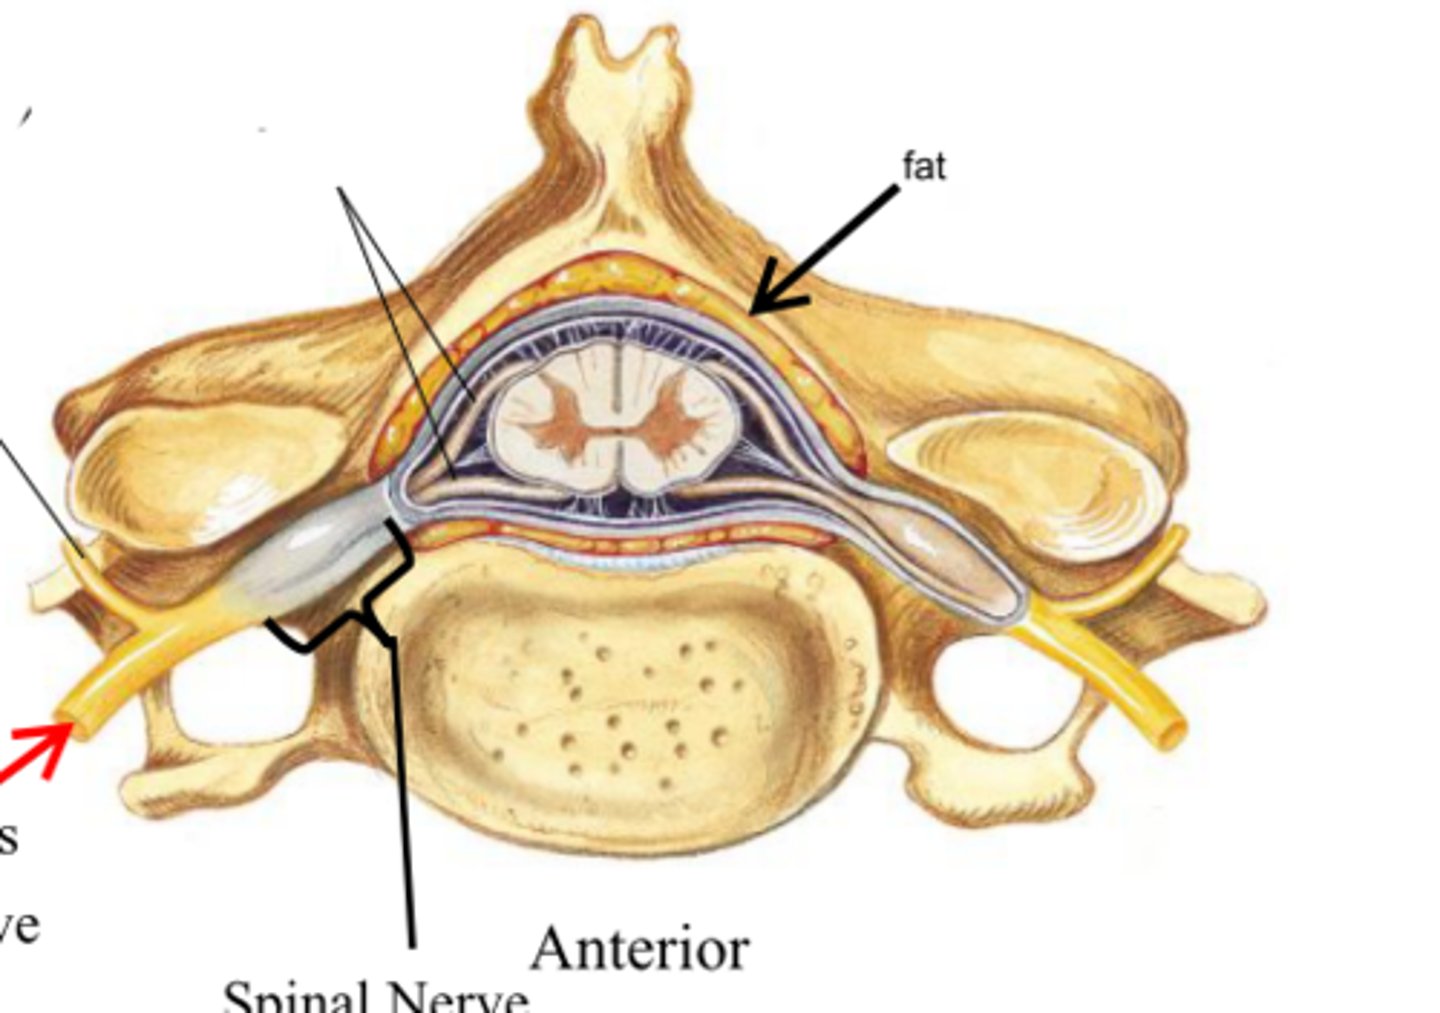

spinal cord

31 pairs of nerves arising from the spinal cord; letter abbreviation for region of spine they originate from; forms where the anterior and posterior roots join; mixed nerves (contain sensory and motor fibers)

posterior (dorsal) rootlets

merge to form a root

posterior (dorsal) root

contains sensory axons

posterior (dorsal) root ganglion

contains cell bodies of sensory neurons

true spinal nerve

anterior root

contains motor axons

spinal meninges

dura mater, arachnoid mater, pia mater (PAD to protect the spinal cord from deep to superficial)

dura mater (spinal cord)

thick, outermost layer of the meninges; 5 on image

arachnoid mater (spinal cord)

middle weblike layer of the meninges; 4 on image

pia mater (spinal cord)

thin, delicate inner membrane of the meninges; 3 on image

central canal of spinal cord

center of spinal cord which contains cerebrospinal fluid

posterior median sulcus

a shallow vertical groove dividing the spinal cord throughout its whole length in the midline posteriorly.

anterior median fissure

a groove along the anterior midline of the spinal cord that incompletely divides it into symmetrical halves

gray matter of the spinal cord

cell bodies, dendrites, and unmyelinated axons arranges in a butterfly shape with anterior and posterior "horns"

posterior (dorsal) horns

contain axons of sensory neurons and cell bodies (sensory nuclei) of interneurons